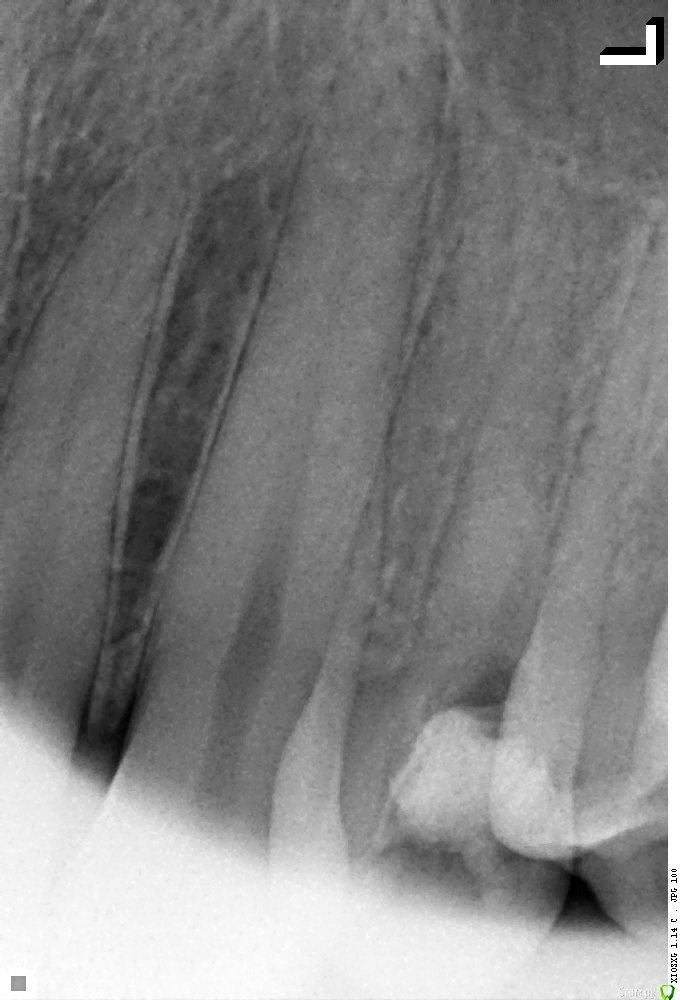

24 зуб

Поставили диагноз периодонтит.

Вскрыли каналы, поставили йод на неделю.

Затем почистили каналы и поставили гуттаперчу.

Рентген После и До лечения: